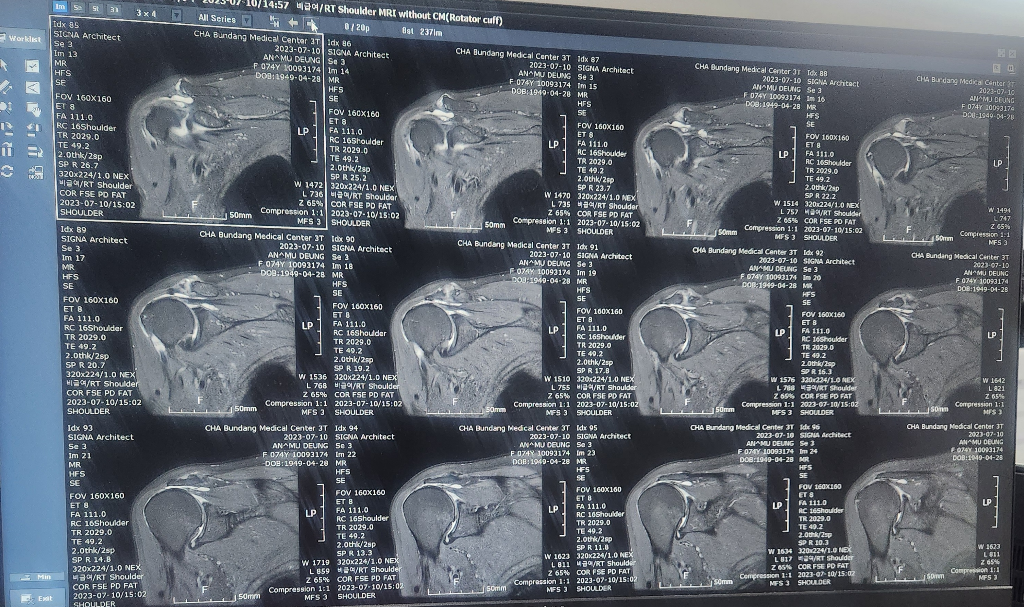

할머니가 넘어지면서 어깨를 다쳤는데

검사만하고 설명은 다음으로 미뤄져서요..

혹시 이 영상만으로 현재 어깨상태 문의드려도될까요

• 3번 째 사진

• 안녕하세요. 이욱현 의사입니다. MRI가 영상이 수백장이 나오기 때문에 사진으로 찍어서 올리신 것으로는 알 수 없습니다. 진료 내용 때문에 다른 의견 (2nd opinion)을 원하시는 경우에는 영상 검사를 copy 해서 다른 병원의원에 결과를 입력하고 진료를 다시 받는 것이 좋습니다.

현재 어깨관절에 물이 차있는 소견으로 염증이 있는 것으로 보이며, 회전근개의 경우는 영상의 크기가 작아 정확한 판단은 어렵겠습니다.